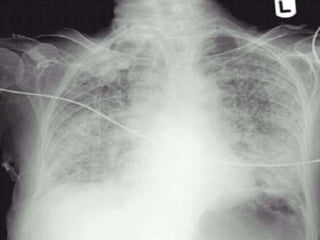

Diseased Lungs Do

Not Fully Collapse,

Despite Tension Pneumothorax

…and

They cannot always

be fully “opened”

Dimensions of a fully

Collapsed Normal Lung